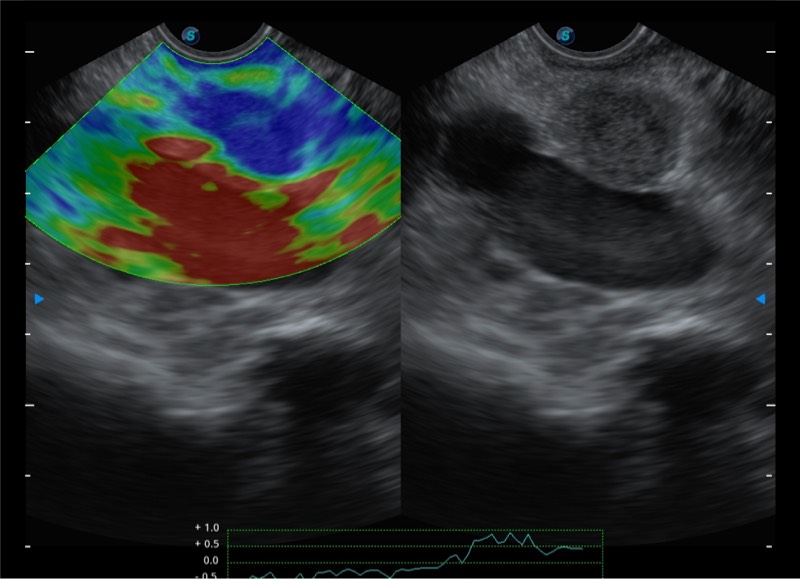

• 搭载百万级CMOS成像技术

• 及自主研发凸阵换能器,

• 可呈现优质的内镜和超声画面

基于二十年的超声技术积累,新葡的京集团8814检测站提供了最新一代的独立超声主机,在提供高质量图像的同时满足多学科使用。具备常见多普勒技术并提供弹性成像、声学造影等高端影像技术。新一代传感器具有更强的抗干扰能力并减少图像伪影。